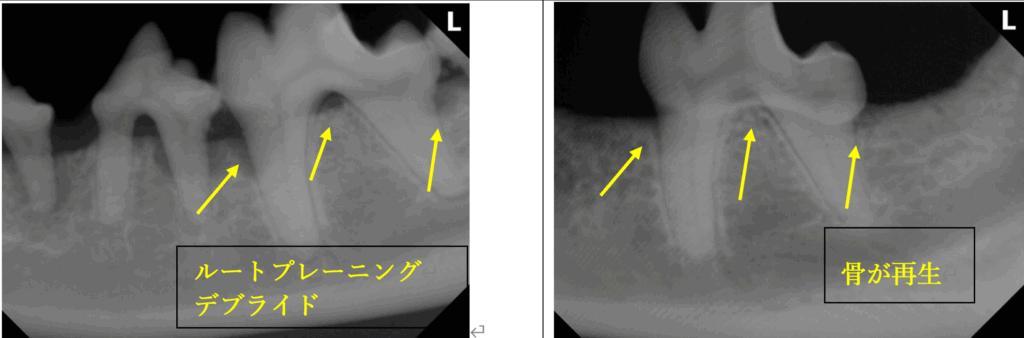

歯周病により炎症を起こしダメージを受けた歯肉と歯槽骨の再生を目指すためには、良質なルートプレーニングとデブライド(歯根部の歯石除去と炎症を起こした肉芽組織の除去)とが必要不可欠です。

適切な処置を施すことで、歯肉と歯槽骨の再生が期待できます。